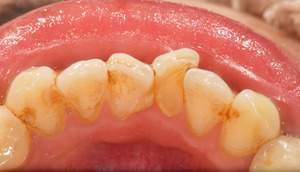

スケーリング

治療前

治療後

| 年齢 | 45歳・男性 |

| 主訴 | 歯石をとりたい |

| 治療内容 | 全顎歯石除去 |

| 治療期間 | 60分 |

| 費用 | 約2,000円(保険適用) (2022年7月現在) |

| 治療方針 | 約4年ぶりの歯科医院で歯のクリーニングを行いたいと来院されました。 歯石除去と歯の表面に付着したプラークを取り除きました。また、ご自身でしっかり歯磨きができるように、歯ブラシのレッスンも行いました。 |

| 担当者所見 | 歯石がなくなった変化に驚き、すっきりしたと喜んでくださいました。歯周病の進行がみられるので次回以降歯周病治療を行っていきます。 |